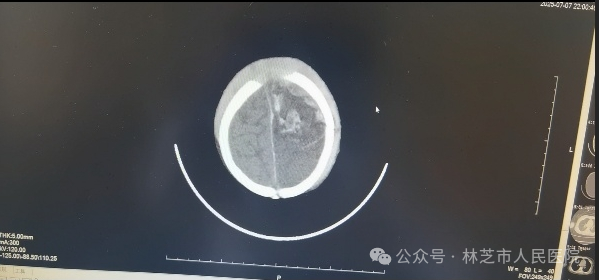

7月7日晚9时,还处于高原适应期的张春敏主任接到儿科值班医生的紧急电话:一名昏迷不醒、呼吸微弱的幼儿被送入医院,双侧瞳孔不等大,生命危在旦夕。尚未克服高原反应的张春敏主任立即电话中指导抢救,顶着高原缺氧的状态急速奔赴医院。查体发现患儿左侧枕部淤肿,凭借丰富经验,他迅速判断患儿存在严重颅脑创伤、颅内出血合并脑疝,当即汇报医院医务科启动绿色通道,连夜联系影像科,并同值班医生护送患儿完成急诊头颅CT检查,确诊为“左侧额颞顶叶脑挫伤、蛛网膜下腔出血、硬膜下/外出血、脑疝”。时间就是生命,张主任立即联系了同批援藏专家神经外科谢韬主任到场评估手术救治。

7月7日晚急诊头颅CT情况